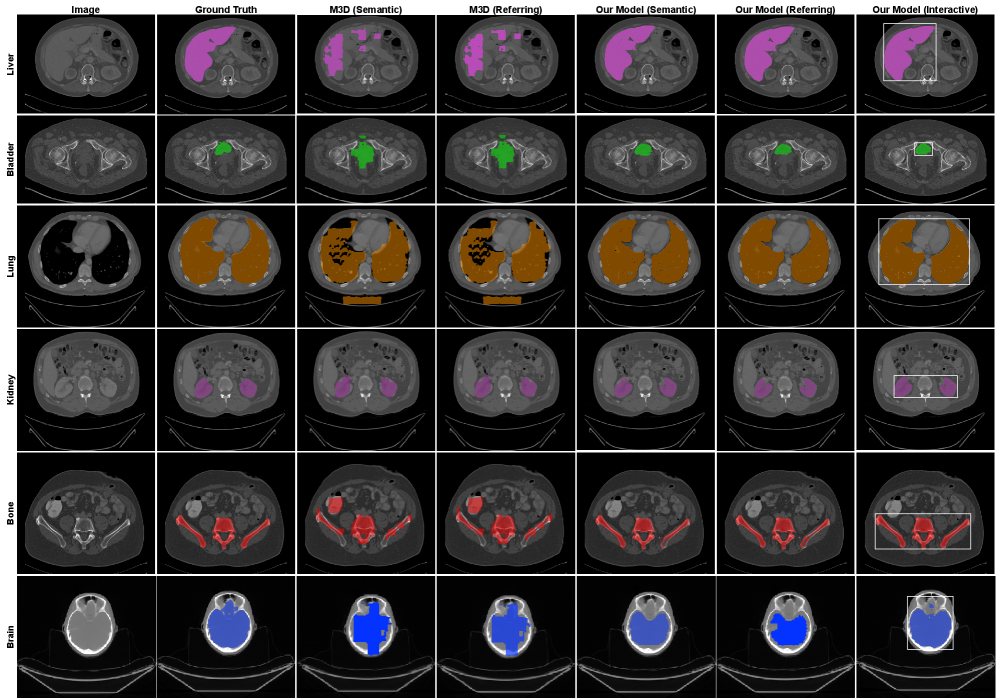

Refer to caption

Figure 4: Comparison of the proposed method with M3D on referring and semantic segmentation. Interactive segmentation results using bounding-box prompts are also included for comparison (CTOrg dataset shown). Liver is shown in magenta, bladder in green, lung in brown, kidney in purple, bone in red, and brain in blue.

5.4 Evaluation on Interactive Segmentation

We further evaluate interactive segmentation on the same dataset and testing protocol as in the referring segmentation experiments. This setting simulates a human-in-the-loop workflow, in which users iteratively refine segmentation masks through additional prompts. Two interaction modes are examined: bounding-box prompting and point prompting. For bounding-box prompting, a random slice is selected from each 3D volume, and a bounding box with slight spatial jitter from the ground truth is provided as input. For point prompting, three randomly sampled positive points within the target region are selected on a random slice. In both settings, the model receives the same image and text inputs as in referring segmentation, augmented with the corresponding visual prompts. Dice coefficient is used as the evaluation metric. Since no existing 3D medical VLMs support interactive segmentation with text-based prompts, our semantic and referring segmentation results serve as baselines. Quantitative results are summarized in Table 5, and qualitative examples for both referring and interactive segmentation are shown in Fig. Fig. 4. Across all datasets, both interactive variants consistently outperform their non-interactive baselines. Bounding-box prompts yield the highest Dice scores, followed by point prompts. These findings demonstrate that incorporating user feedback substantially improves segmentation quality.

We also observe that interactive refinement yielded modest improvements on CTOrg and ACT-1K. Both datasets consist primarily of large, well-defined organs (e.g., liver, lungs, kidneys), for which the language-driven [SEG] token already encodes rich spatial and semantic cues from the volumetric context. As a result, adding point or bounding-box prompts provides only incremental gains, since the model can infer coarse boundaries directly from language descriptions. In contrast, results on the TotalSegmentator dataset exhibit a larger improvement. This dataset is considerably more challenging, as it contains numerous small and complex anatomical structures, such as vertebrae, ribs, and vessels. For these fine-grained regions, the global language representation may lack sufficient spatial specificity, leading to under- or over-segmentation when relying solely on text. In these cases, explicit interactive prompts supply critical spatial priors, enabling the model to localize small anatomical regions more precisely. Overall, these findings highlight the complementary role of interactive segmentation in clinical workflows: while large structures can often be segmented reliably from language alone, small or complex anatomical targets benefit significantly from user-guided refinement, making the model more practical and adaptable for real-world clinical workflows.